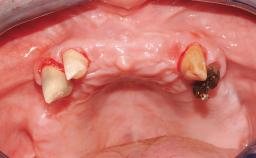

Transition from an “irrational to treat” Maxillary Dentition to a Full-Arch Segmented FDP by Early Loading of Eight Implants Placed Using the Staged Approach

The staged approach permits the transition from an “irrational to treat”dentition to a full arch implant supported restoration without any need to use a removable provisional prosthesis or to apply the immediate-placement and immediate-loading techniques.  A failing dentition is the usual indication for a staged treatment. On the other hand, the dentition should still contain many residual teeth, but with few or none of them being suitable for use as definitive abutments for a full-arch fixed restoration.This situation is usually the result of advanced periodontal disease or of the failure of an extensive fixed prosthesis.

Periodontal Status History of periodontitis or genetic predisposition